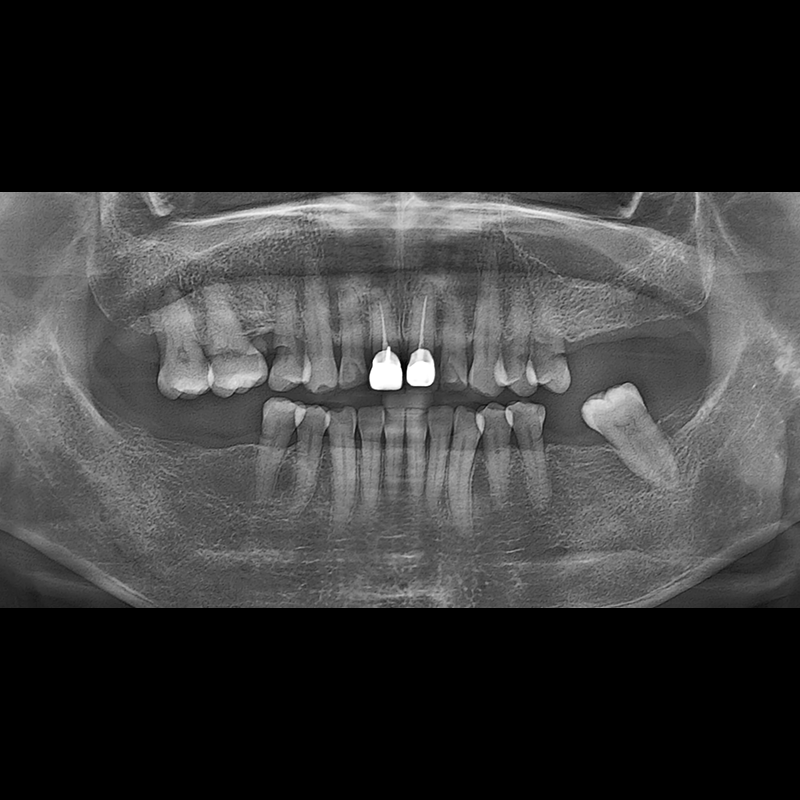

BEFORE AFTER

임플란트 전후사진 2025.05.30

결손된 치아 부분과 살리기 힘든 치아 위치에 임플란트를 식립하였습니다.